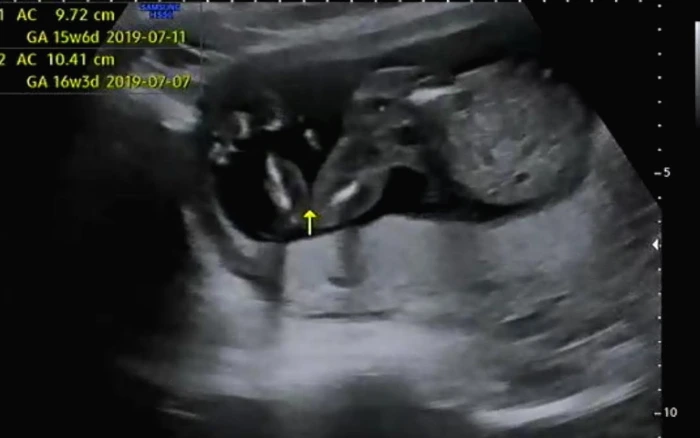

BPD(태아의 머리둘레)와 AC(태아의 복부둘레)를 측정하고 이후 심장소리를 확인했다. BPD와 AC로 이용하여 주수에 맞게 잘 자라고 있는지 확인했다. 아기는 여전히 잘 자라고 있다고 일정하게 심장소리를 들려주며 초음파 상으로 열심히 움직이고 있었다.